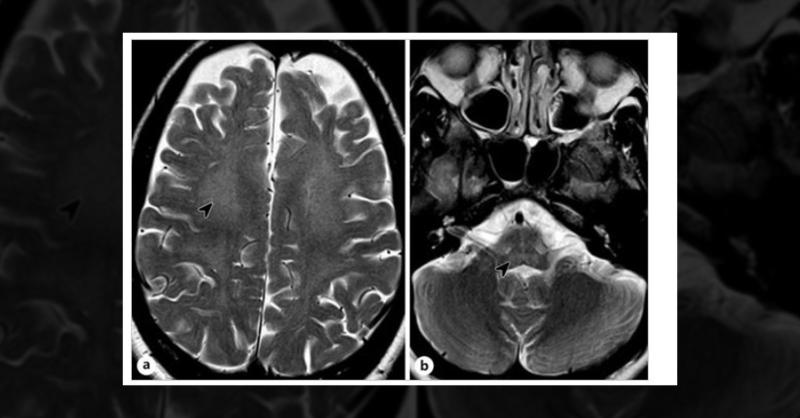

What is the Cause of the Patient’s Adult-Onset Progressive Cerebellar Ataxia?

A 39-year-old woman presented with a 1.5-year history of worsening right arm tremor and coordination problems, limiting her daily activities. She had no issues with walking or falls but had a history of learning difficulties, right eye cataracts, and secondary amenorrhea. Her sister recalled neonatal diarrhea and vomiting treated with a temporary l